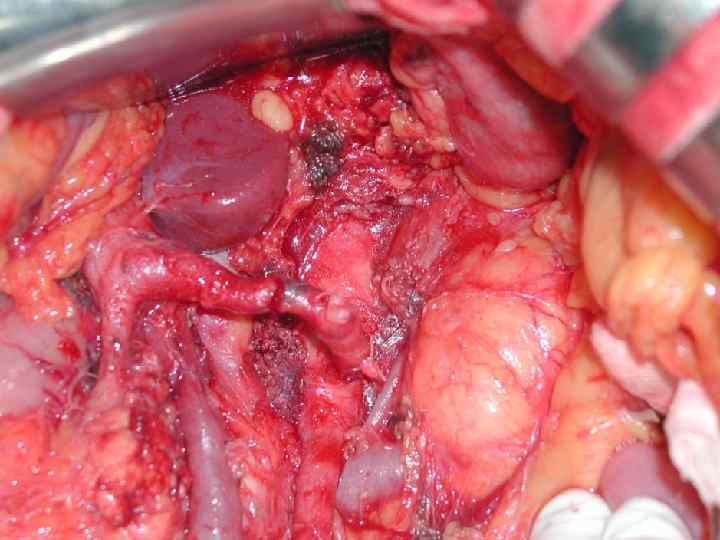

Инвазия чревного ствола и общей печеночной артерии

Резекция чревного ствола и общей печёночной артерии при выполнении ДСРПЖ Вид резекции Циркулярная резекция чревного ствола Всего Число больных с пластикой 4 без пластики 11 15

Верхняя мезентерикография после резекции чревного ствола с ушиванием обоих концов сосуда наглухо. Кровоснабжение печени осуществляется через гастродуоденальную артерию